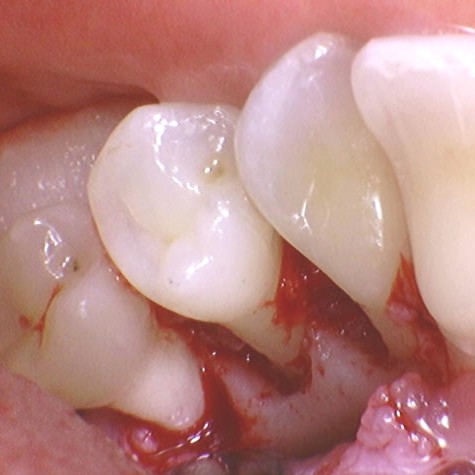

• Patientvurdering og parodontal diagnostik

• Systematisk journaloptag, risikovurdering og kliniske målinger

• Sådan stiller du en præcis og brugbar diagnose